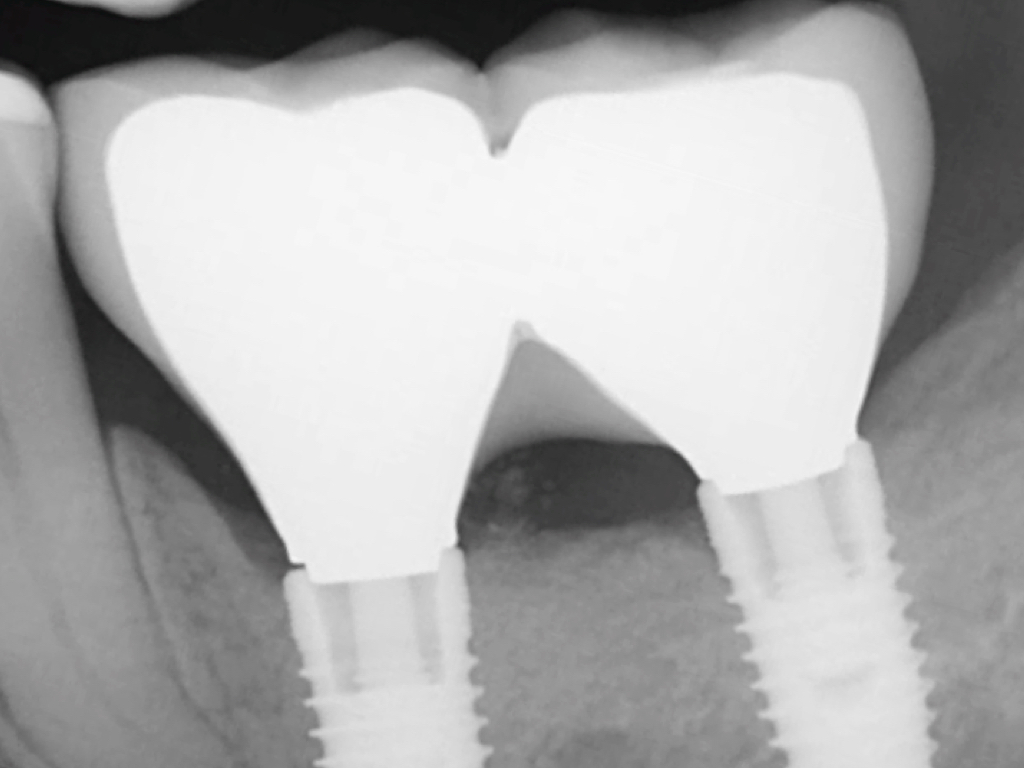

Similar to natural teeth, measurements of PPD and BoP before and after treatment are clinical parameters often used to determine the health of dental implants (Figure 4 and Figure 5). However, due to the difference between periodontal and peri-implant anatomy, concerns have been raised about the use of probes in peri-implant tissues around dental implants. These include the risk of peri-implant tissue damage,17,18 risk of damage to the implant surface by the metallic probe,19-21 risk of bacteria inoculation,22-27 and risk of galvanic corrosion resulting from contact between two dissimilar metals.21,28-30 These risks are discussed in the following sections.

Probing the sulcular depth around a dental implant is an important clinical exercise to assess implant health and stability. Longitudinal measurement of probing depth helps monitor the integrity of the peri-implant tissues. An increase in the probing depth usually indicates loss of alveolar bone support. Increasing probing depth over time in the presence of BoP and gingival exudate are criteria to diagnose peri-implant disease.33 Increased probing depth accompanied by BoP without concomitant bone loss has been defined as peri-implant mucositis.34 When these signs are present with radiographic (or sounding) evidence of bone loss, the disease has been defined as peri-implantitis.34

Probing is useful to determine the presence of biological complications at the buccal and lingual sites of implants, which cannot be evaluated on a radiograph (Figure 6 through Figure 8). Because of the absence of a periodontal ligament, bone loss on the buccal and lingual aspects of an implant indicates loss of support for the implant and may be a sign of additional circumferential bone loss around the implant.35

Fig 5. Bone loss shown on radiograph confirms the presence of peri-implantitis and peri-mucositis.

Figure 5